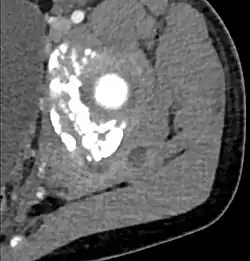

Additional images

-

CT with IV contrast showing enlargement and heterogeneous hypodensity in the right pectoralis major muscle. A focal abscess collection with gas within it is present medially. There are enlarged axillary lymph nodes and some extension into the right hemithorax. Note the soft tissue and phlegmon surrounding the right internal mammary artery and vein. The patient was HIV+ and the pyomyositis is believed to be due to direct inoculation of the muscle related to parenteral drug abuse. The patient admitted to being a "pocket shooter" -